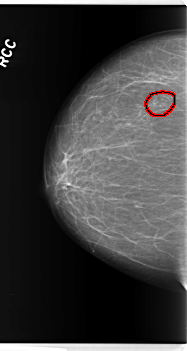

C_0276_1.RIGHT_CC

RIGHT_CC LINES 5952 PIXELS_PER_LINE 3168 BITS_PER_PIXEL 12 RESOLUTION 50 OVERLAY

FILE: C_0276_1.RIGHT_CC.OVERLAY

TOTAL_ABNORMALITIES 1

ABNORMALITY 1

LESION_TYPE CALCIFICATION TYPE PLEOMORPHIC DISTRIBUTION CLUSTERED

ASSESSMENT 4

SUBTLETY 4

PATHOLOGY BENIGN

TOTAL_OUTLINES 1

BOUNDARY